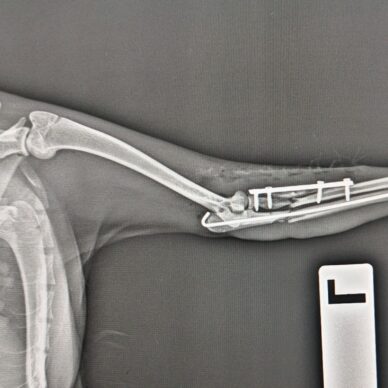

Ortopedi Cerrahi

Kedi ve köpeklerde ortopedi cerrahisinde başarı